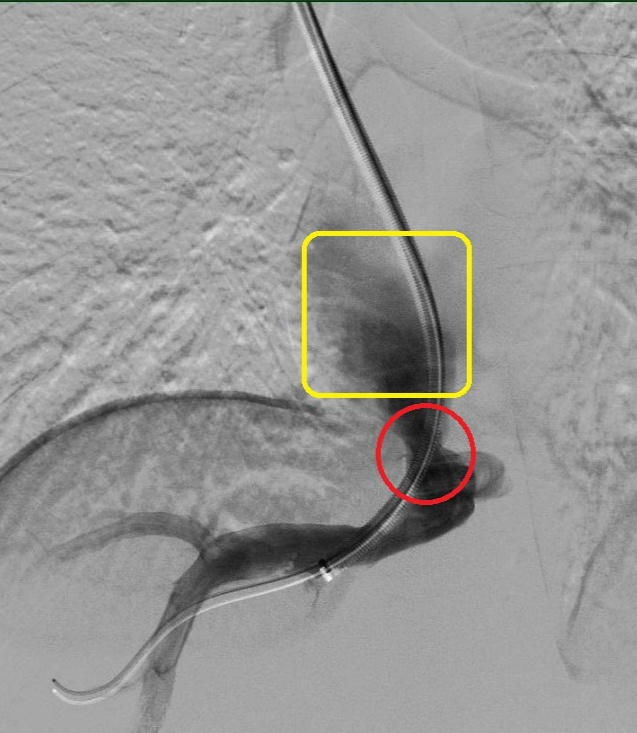

红色圈内为病变的静脉,可见血管极其狭窄,远端黄色方框内未见明显血流通过。

红色圈内为打通后的静脉,可见血管较前明显增宽,远端黄色方框内可见大量血流通过。